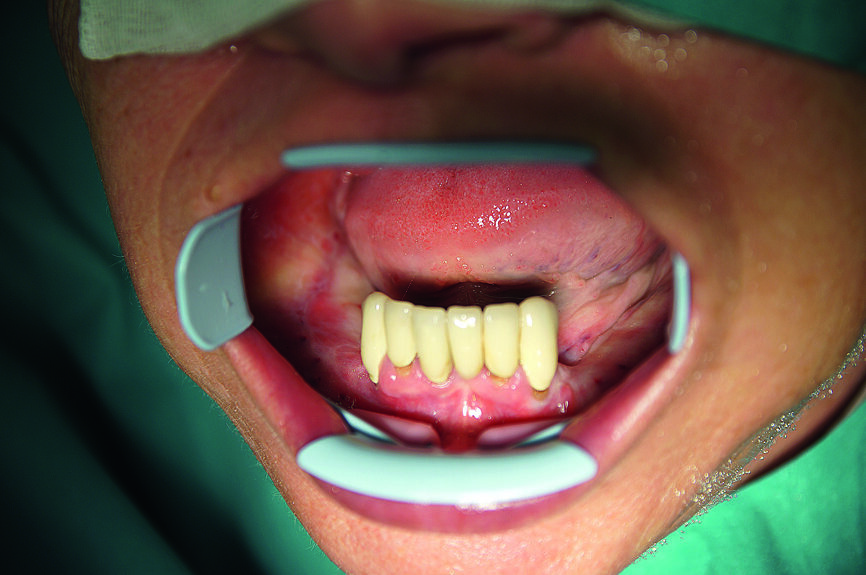

Fig. 6 : Vue préopératoire de la mandibule.

En raison de la chirurgie tumorale antérieure, l’anatomie de la cavité buccale s’était fondamentalement modifiée : en raison d’une xérostomie et de la survenue de caries induites par les rayons en 2013, toutes les dents encore présentes dans les deux arcades avaient dû être extraites. L’examen clinique initial réalisé dans notre service a montré deux arcades totalement édentées, avec perte du goût et xérostomie.